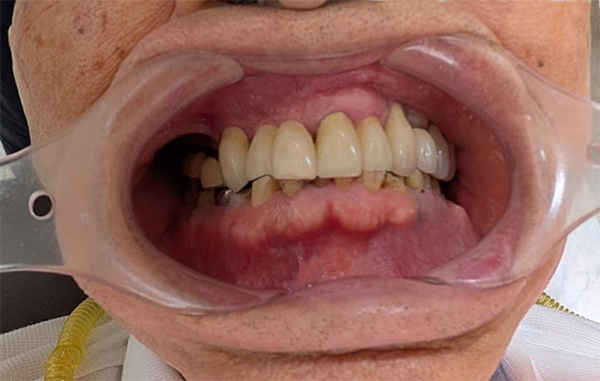

インプラントの長期症例

掲載写真撮影:2025年(95歳/男性)

左下インプラント:1994年(年前)インプラント埋入 当時64歳

右上インプラント:2002年(年前)インプラント埋入 当時72歳

前歯・左上インプラント:2010年(年前)インプラント埋入 当時80歳

95歳(2025年現在)・・・・シッカリ噛めていて顔に張りがあります

※上顎 インプラントでなければ多数歯の入れ歯が選択肢